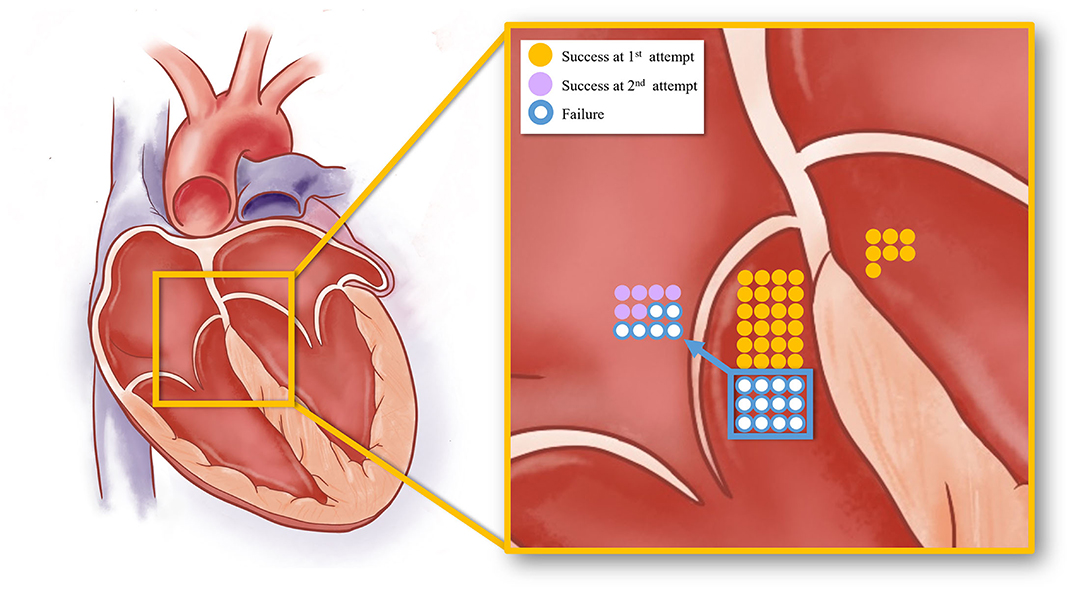

Figure 5. The schematic diagram showing the acute procedural results of right and left PHVA ablation. The yellow dots represented successful cases by the B-SLTV approach and those by trans-aortic retrograde ablation. The purple dots represented success cases by the adjunctive A-SLTV approach. White dots represented cases with ablation failure.

Right PHVA Ablation

RF ablation by the B-SLTV approach succeeded in 24 (66.7%) of 36 patients with right PHVA, and failed in the remaining 12 patients (Figure 5). The electrocardiographic and procedural data were compared between successful and unsuccessful B-SLTV ablation in Table 2. There was significant greater target -HB distance and lower prevalence of junctional beats in patients with successful B-SLTV ablation than in those without. ECG morphologies, the local ventricular activation preceding QRS onset (V-QRS), proportion of small HB potential at the target, average RF power, RF duration, number of RF delivery and fluoroscopy time were comparable between successful and unsuccessful B-SLTV ablation.

Subsequent ablation in 12 patients with unsuccessful B-SLTV ablation was listed in detail in Supplementary Table 1. A-SLTV ablation successfully abolished the clinical VA in 6 of them. Totally procedural success was achieved in 30 (83.3%) of 36 patients with right PHVA. The remaining 6 patients experienced ablation failure even after thorough mapping and ablation at the neighboring structures (RVOT and three coronary cusps at the aortic root) and the left- parahisian region.

Left PHVA Ablation

Sub-aortic valve ablation was successful in all seven patients with left PHVA. In each of 4 patients with failed right parahisian ablation, the V-QRS time at the left-sided target was greater than that at the right-sided target (27 vs. 24, 31 vs. 29, 16 vs. 14, 33 vs. 31 ms, respectively). Compared with right PHVA, left PHVA exhibited higher proportion of precordial transition ≤lead V2 and lower proportion of QS shape in lead V1 on ECG recordings (Table 2). The procedural parameters were comparable except that the target-HB distance was greater in left sided group than that in right-sided group.

At the end of 12 months' follow-up, clinical success was achieved in 27 (75%) of 36 patients with right PHVA and in 6 (85.7%) of 7 patients with left PHVA. In this PHVA cohort, totally the clinical success was achieved in 33 (76.7%) of 43 patients off AADs by using this systemic mapping approach.